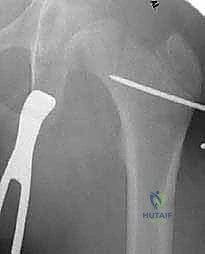

يتم وضع المريض على طاولة عمليات خاصة (Fracture Table) تسمح باستخدام جهاز الأشعة السينية الفلوروسكوبي (C-arm) أثناء الجراحة لمراقبة كل خطوة بشكل مباشر.

3. إدخال سلك الدليل (Guide Wire Placement)

هذه هي الخطوة الأكثر أهمية. باستخدام الأشعة المباشرة، يقوم الدكتور بإدخال سلك معدني رفيع في عنق عظم الفخذ باتجاه الرأس. يتم وضع هذا السلك بزاوية محسوبة مسبقاً بدقة متناهية لتتطابق مع زاوية الشريحة (90 درجة).

4. تحضير مسار الشريحة النصلية (Seating Chisel)

باستخدام أداة خاصة تشبه الإزميل، يتم حفر مسار دقيق داخل العظم الإسفنجي لعنق الفخذ، وذلك تمهيداً لإدخال نصل الشريحة المعدنية.

5. قطع العظم (The Osteotomy)

باستخدام منشار جراحي عالي الدقة، يقوم الدكتور هطيف بقطع عظم الفخذ أسفل منطقة المدور الكبير (Subtrochanteric). في هذه المرحلة، يتم إزالة إسفين عظمي صغير (Wedge) بالزاوية المطلوبة لتصحيح التشوه.

6. إدخال الشريحة والتثبيت (Plate Insertion & Fixation)

يتم إدخال نصل الشريحة ذات الزاوية 90 درجة في المسار الذي تم تحضيره في عنق الفخذ. ثم يتم ضم جزئي العظم المقطوعين معاً (إغلاق الفجوة)، مما يؤدي فوراً إلى تغيير زاوية عنق الفخذ إلى الوضع الطبيعي الجديد. يتم تثبيت الجزء الطويل من الشريحة على جسم عظم الفخذ باستخدام براغي قوية من التيتانيوم أو الفولاذ الطبي المقاوم للصدأ.